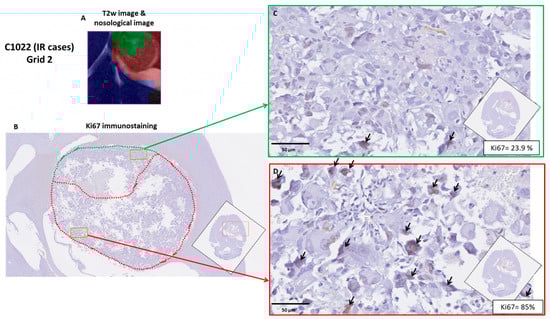

2.4. Histopathology Validation

3.3. Histopathology Results

| Case | Ki67% ± SD (Green Fields) | Ki67% ± SD (Red Fields) | Ki67% ± SD (Global) | TRI% | Classification by TRI Criteria |

|---|---|---|---|---|---|

| C971 | 17.2 ± 16.8 | 25.7 ± 17.0 | 22.0 ± 17.2 | 44.1 | Intermediate |

| C1022 | 19.0 ± 20.9 | 54.9 ± 32.6 * | 42.5 ± 33.5 | 46.5 | Intermediate |

| C1026 | 53.5 ± 30.3 | 73.0 ± 26.8 | 66.0 ± 39.1 | 38.9 | Intermediate |

| C979 | n.a. | 64.8 ± 7.3 | 64.8 ± 7.3 | 3.3 | Low |

| C1100 | 82.9 ± 4.6 | 92.5 ± 0.6 | 82.2 ± 7.7 | 66.3 | High |

| C1108 | 75.1 ± 9.5 | 75.8 ± 0.2 | 79.3 ± 10.1 | 70.3 | High |

| C1110 | n.a. | 63.9 ± 13.0 | 63.9 ± 13.0 | 0 | Control |

| C1111 | n.a. | 73.3 ± 6.4 | 73.3 ± 6.4 | 0 | Control |